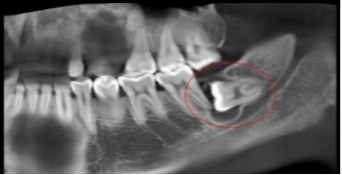

5、邻牙及支持组织的吸收:当阻生的智齿萌出过程中受阻于第二磨牙时,会引发第二磨牙牙根牙根逐渐吸收,严重者可使下颌第二磨牙远中牙根完全吸收,致第二磨牙松动、疼痛,常常食物嵌塞发生慢性牙周炎,也会造成牙槽骨的炎症性吸收,使第二磨牙反复肿痛。

7、智齿周围囊性病变:下颌阻生的智齿常常形成囊肿,引起骨头吸收。

1、反复发作的冠周炎:智齿牙冠周围软组织与牙齿之间形成一盲袋,引起食物、细菌的积存,抵抗力下降时,出现冠周炎症发生。常表现为冠周组织红肿疼痛,以致影响咀嚼,吞咽,还常伴有张口困难及发烧,巴结肿大等全身症状。若炎症未及时控制,还可向颌周、颈部扩散,形成组织间感染、颌骨骨髓炎,甚至还可发生败血症、心包炎等严重全身并发症。